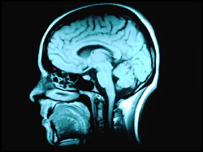

انسانی دماغ

عمر کے ساتھ ایک صحتمند انسان کی ذہنی چستی کم ہوجاتی ہے

امریکی یونیورسٹی ہارورڈ سے تعلق رکھنے والے سائنسدانوں کو میڈیکل امیجنگ تکینک کے استعمال سے اٹھارہ سے ترانوے برس کی درمیانی عمر کے ترانوے صحتمند افراد کے دماغ کا موازنہ کرنے کے بعد یہ بات معلوم ہوئی ہے۔

ان افراد کے دماغ کے سکین سے یہ بات سامنے آئی کہ عمر کے بڑھنے کے ساتھ ساتھ دماغ میں وہ مادہ کم ہونا شروع ہو جاتا ہے جو دماغ کے اہم حصوں کے باہمی رابطے کے لیے ضروری ہوتا ہے۔

’نیورون‘ میں شائع ہونے والی اس تحقیق کے مطابق اس کمی سے یادداشت اور ذہن نشینی کی صلاحیتیں متاثر ہونے لگتی ہیں۔ سائنسدانوں کے مطابق اس دریافت سے ممکنہ طور پر اس بات کا جواب بھی مل گیا ہے کہ بڑھتی عمر کے ساتھ ایک صحتمند انسان کی ذہنی چستی کیوں کم ہوجاتی ہے۔